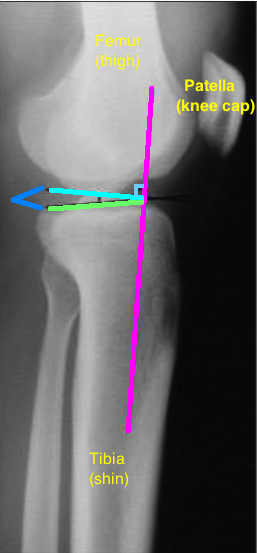

← Understanding why your tibial slope can increase your odds of ACL injury